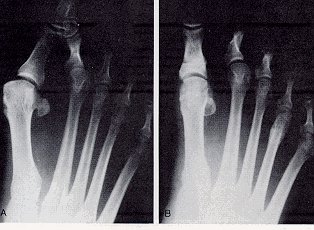

Deformities of moderate abducto valgus have a hallux abductus angle between 20° and 40° and a first intermetatarsal angle of 8° to 15°. In moderate hallux abducto valgus cases, the first MPJ position is generally deviated (Fig. 2).

Figure 2

An example of a moderate HAV deformity

1. The preoperative radiograph.

2. The same patient 3 years after surgery.